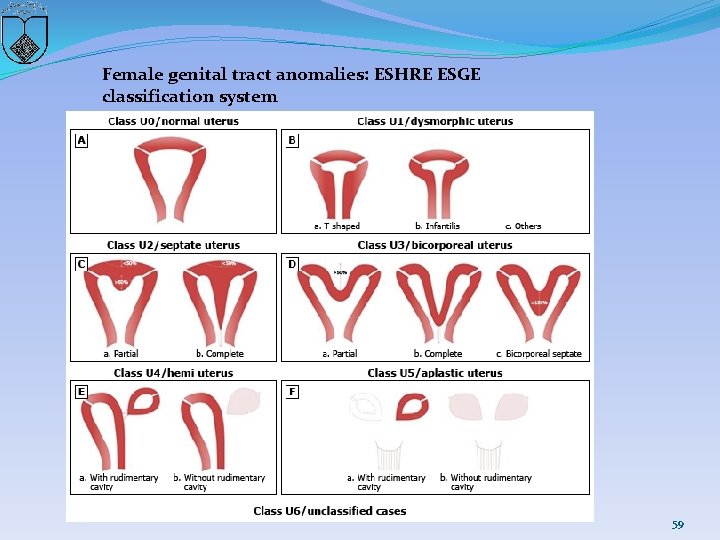

Female genital tract anomalies: ESHRE ESGE classification system 59